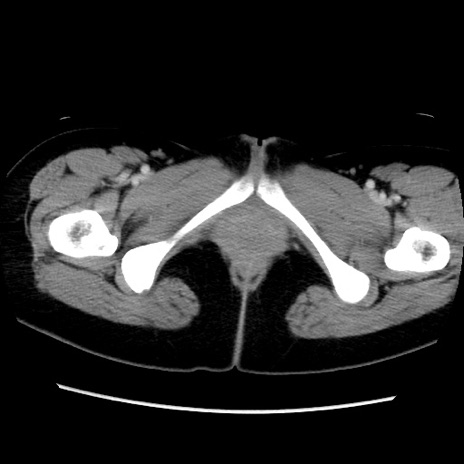

症例39(横断像)

【症例】40歳代女性

【主訴】上下腹部痛

【現病歴】2日目から下腹部痛あり。夜間は痛みで眠れなかった。昨日より上腹部痛と下痢が出現。臥位で痛みは軽快したため、休んでいた。本日になって臥位でも立位でも痛みが強くなってきたため救急要請。

【既往歴】子宮内膜症

【身体所見】部:平坦・軟、左上下腹部に圧痛あり、反跳痛あり。

【データ】WBC 21800、CRP 26.78